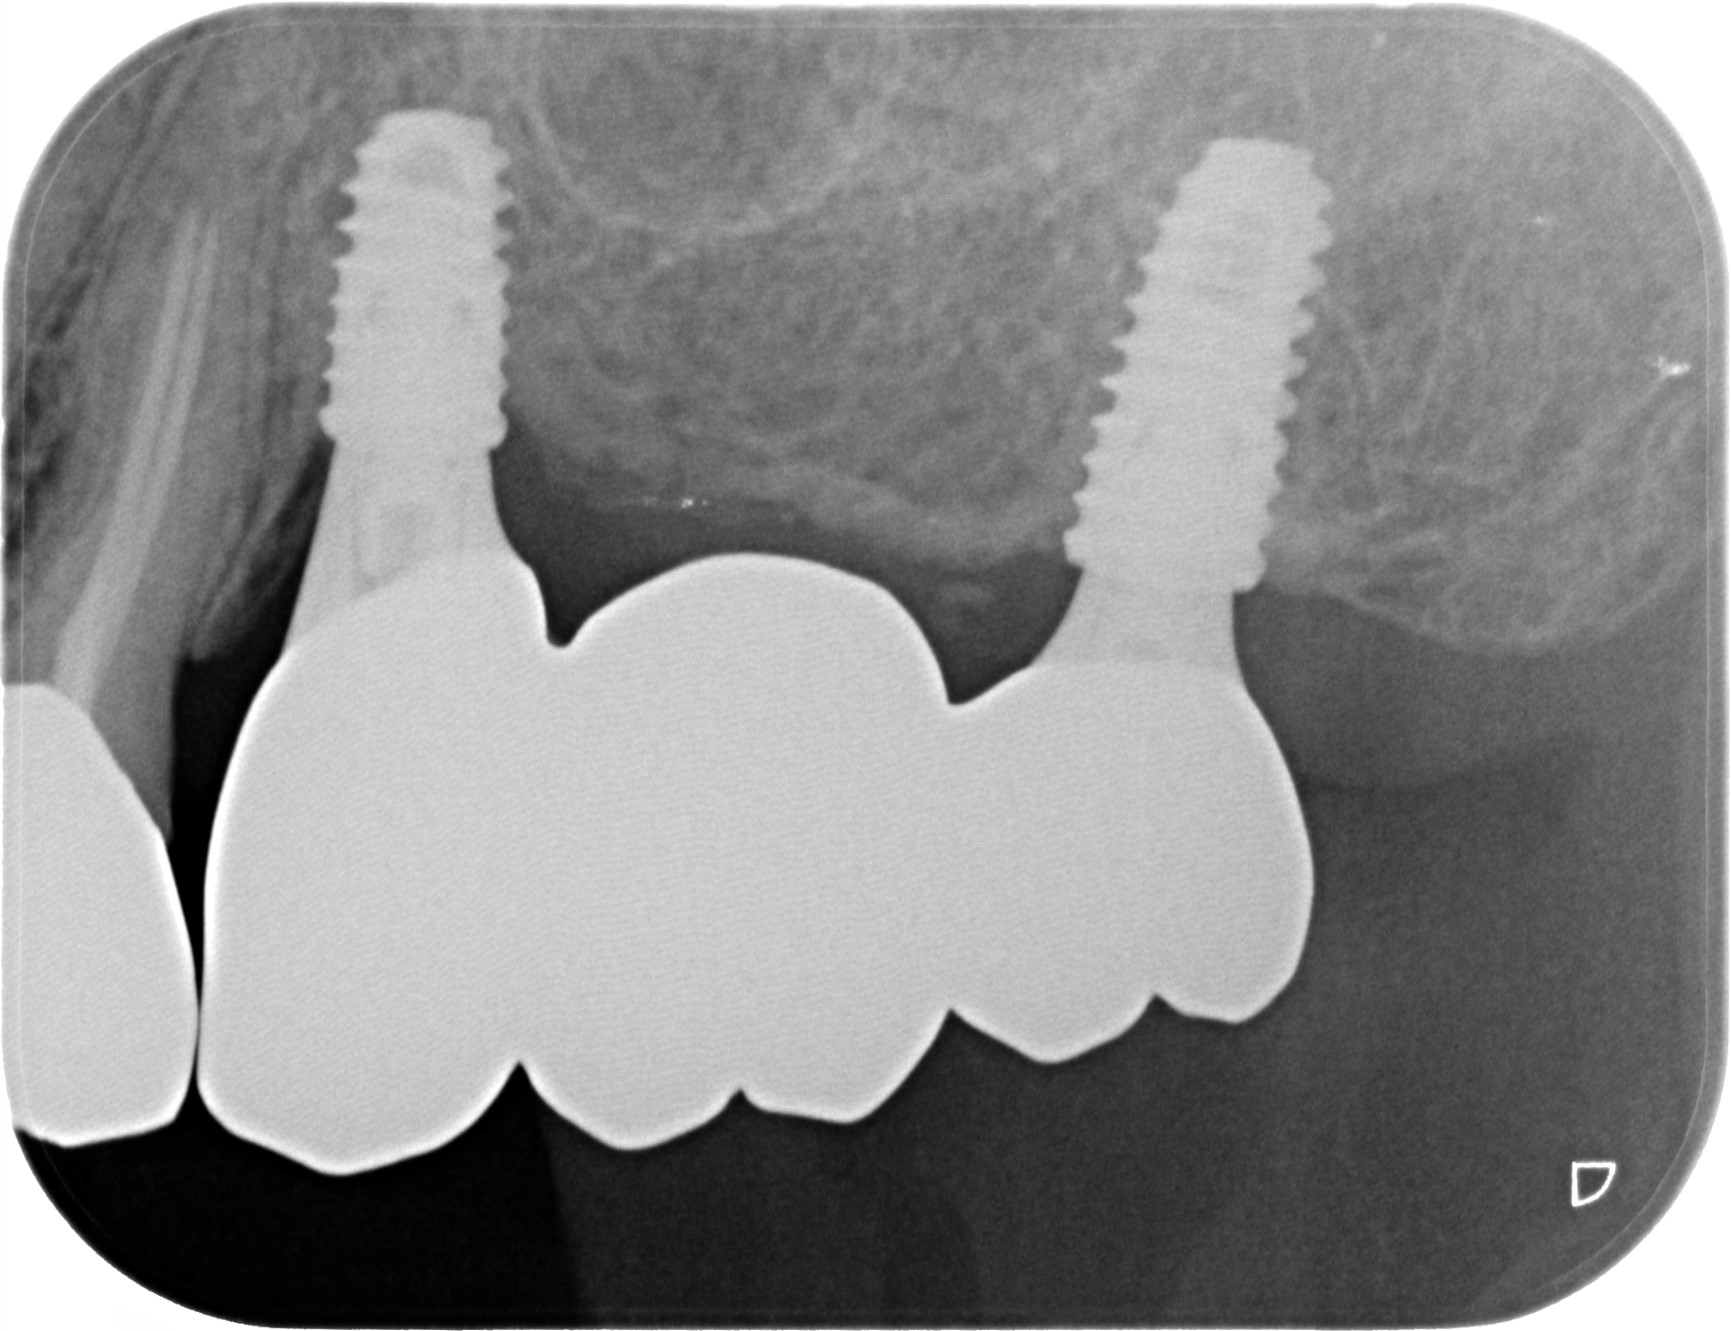

レントゲン写真

- 右下56番パーシャルデンチャー部のインプラント治療

- 右下56番にパーシャルデンチャーを装着しており機能及び審美的に問題を抱えている。

- まず、CT撮影による精密な骨の分析・治療計画を立てガイドを使いインプラント埋入しインプラントが骨と結合するのを待つ間に仮の歯を入れます。その後本歯を作成して装着しました。

- インプラント埋入からジルコニアセットまで三か月半

※自由診療となります - ■総額:¥660,000(税込み) ■内訳:埋入(ガイド込み)¥200,000×2、仮歯¥20,000×2、被せ物¥80,000×2